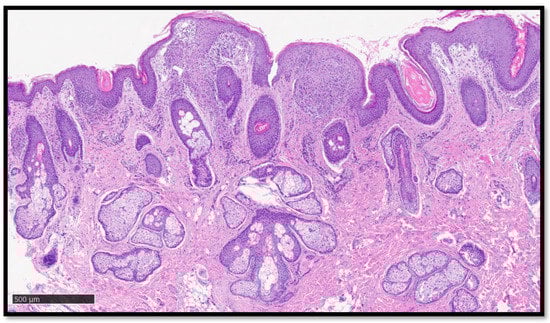

Cutaneous Sarcoidosis-like Eruption Following Second Dose of Moderna mRNA-1273 Vaccine: Case or Relationship?

Cazzato, G.; Ambrogio, F.; Foti, C.; Capuzzolo, M.; Trilli, I.; Casatta, N.; Lupo, C.; Carrieri, M.; Daini, D.; Colagrande, A.; et al. Cutaneous Sarcoidosis-like Eruption Following Second Dose of Moderna mRNA-1273 Vaccine: Case or Relationship? Diagnostics 2023, 13, 1286. https://doi.org/10.3390/diagnostics13071286